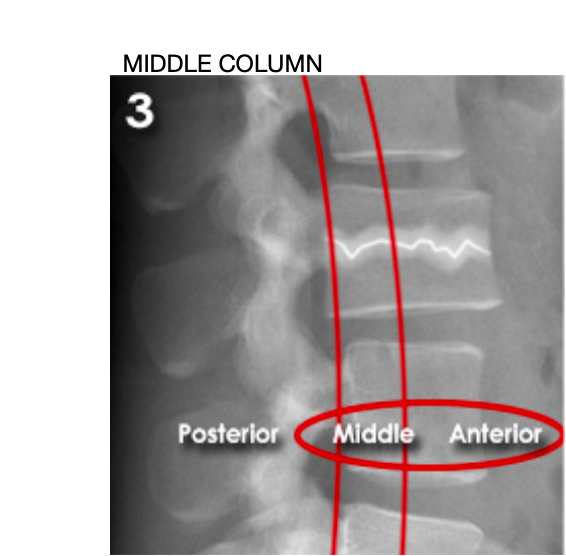

Lumbar three column model

Divides the spine into three columns: anterior, middle, and posterior

Used to determine the stability of thoraco-lumbar spine fractures

severity depends on how many columns are implicated

If spinal instability is suspected further imaging with CT or MRI should be considered

MIDDLE (unstable):

'Burst' fracture (vertebral body crushed in all directions) due to axial loading

between middle of vertebral body to posterior longitudinal ligament